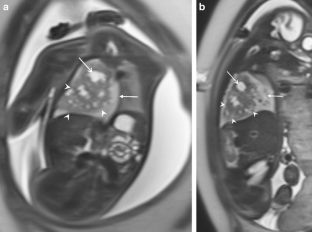

Congenital pulmonary airway malformation (CPAM) is classified into pathologically different types. These types are sometimes distinguishable by fetal lung MRI and are usually observed as higher-signal lesions on T2-weighted images than normal lung. We describe a case of unusual CPAM resembling neoplasms, with a lower signal than is found in normal lung. Histopathology showed a large number of mucogenic cells but found no evidence that could explain this feature on fetal MRI. An unusual low-signal mass associated with a pulmonary cyst in fetal lung on MRI may suggest an unusual type 1 CPAM.

Fig. 1